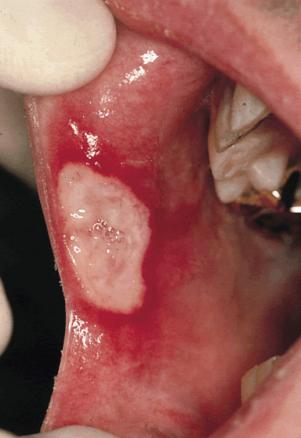

Aphtose buccale

2. Aphtose buccale